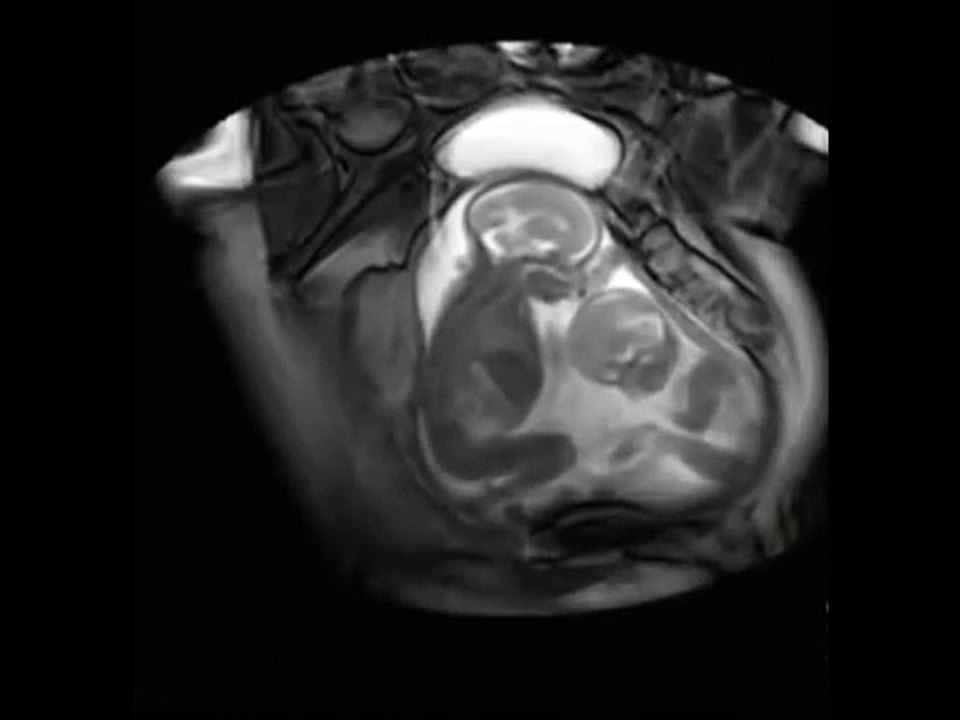

Doi bebeluși au fost surprinși în burtica mamei lor în timp ce se jucau. Este cel mai frumos lucru pe care l-am văzut! 1:34

Doi bebeluși au fost surprinși în burtica mamei lor în ...

Viral Videos 303 views